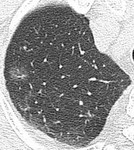

[画像診断]気胸の肺虚脱度について 【研修医と学ぶ】 2010-08-03